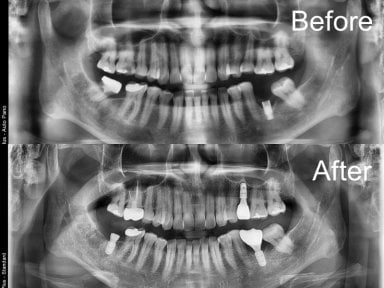

Korean dental clinics routinely use 3D CBCT scans, digital impressions, and computer-guided implant placement. These tools make treatment safer, faster, and more accurate.

After an initial consultation and 3D scan, the dentist plants an implant into the jawbone. If needed, specialists perform bone grafting or sinus lifting at this stage.

- Check reviews and patient photos. Look for real before-and-after cases and feedback from international patients.